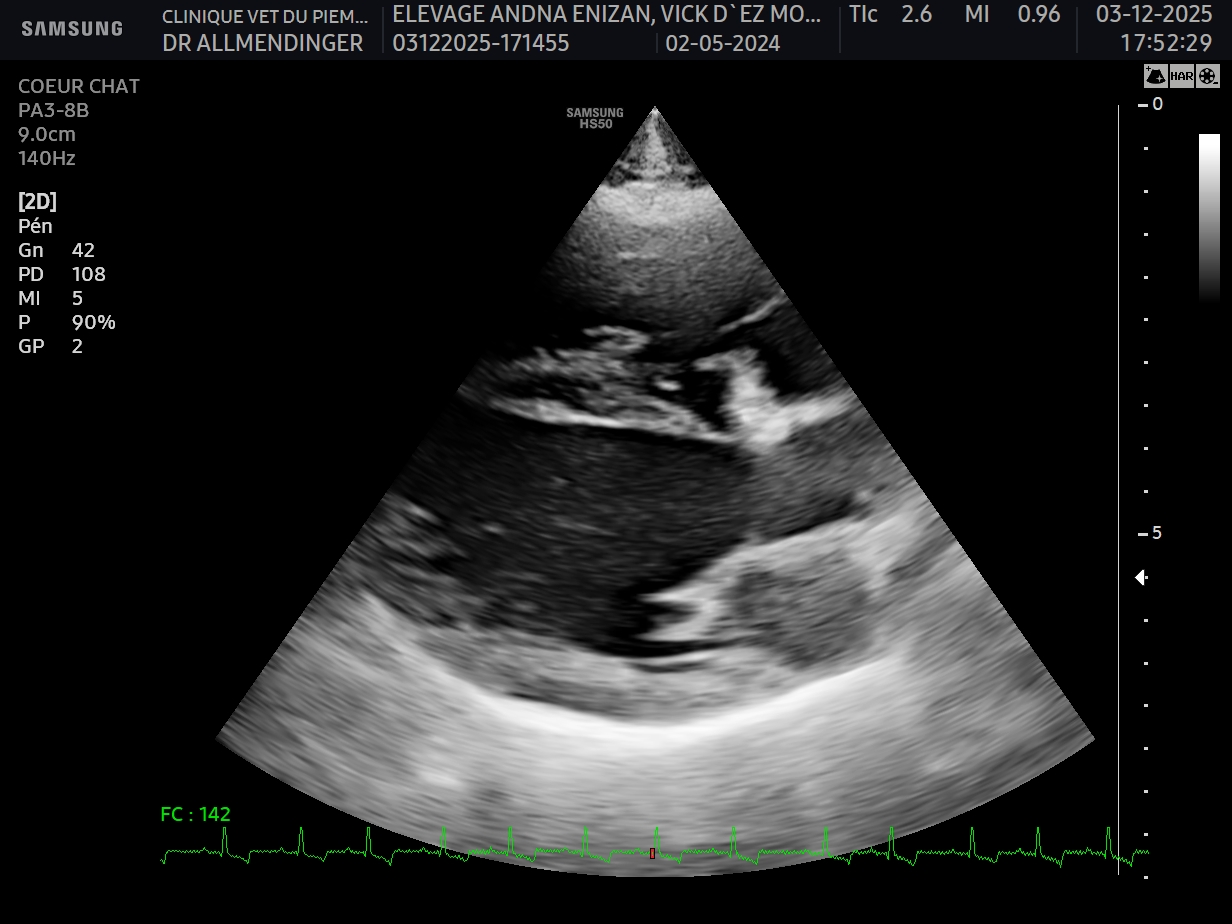

Geste technique : Mesure échographique du LA/Ao (rapport oreillette gauche/aorte)

- Connaître les principales causes de souffle chez le chat et leuyr prévalence

- Connaître les limites de l’examen sanguin pour l’exploration d’un souffle asymptomatique chez le chat

- Connaître les risques associée à la présence d’une CMH asymptomatique chez le chat